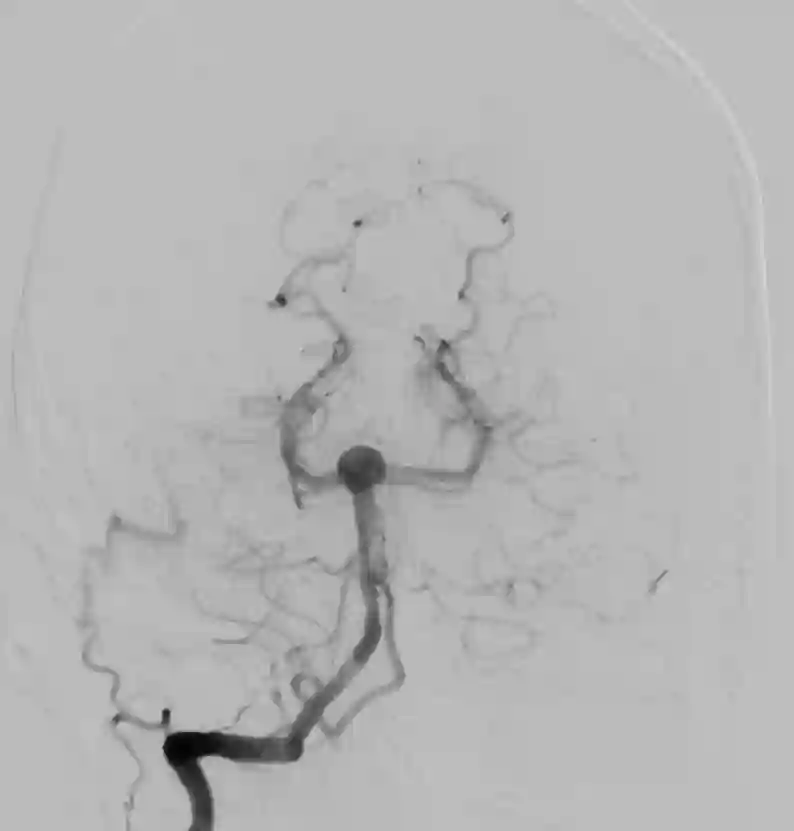

Der Goldstandard in der Diagnose von Basilarisspitzenaneurysmen ist die digitale Subtraktionsangiographie.

Videos

- Video Beschreibung

- Video einer endovaskulären Versorgung eines Basilarisspitzenaneurysmas mit einem WEB Device.